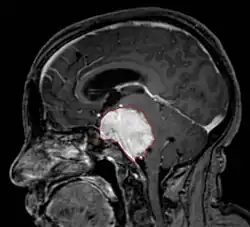

MRI sken se zřetelným meningeomem | |

Meningeom je benigní (vzácně i maligní forma zvaná meningosarkom) nádor mozkového obalu, který roste z pavučnice. Představují zhruba 15–20 % všech vnitrolebních nádorů. Léčba probíhá obvykle radikálním neurochirurgickým odstraněním, hůře dostupné nádory mohou být operovány za pomoci Leksellova gama nože nebo ozařováním.